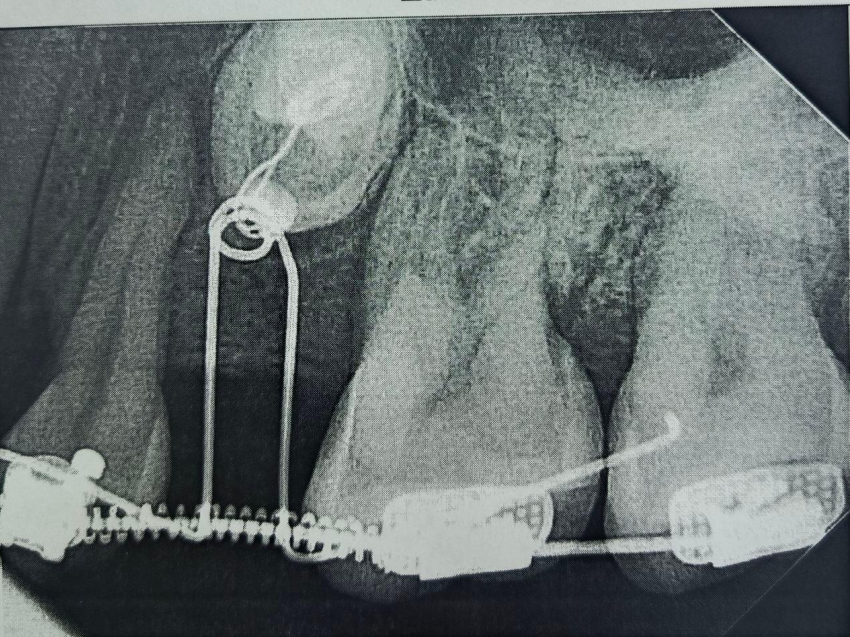

Диагностика с помощью компьютерной томографии показала сложную картину – в челюсти находились два непрорезавшихся зуба.

При этом, в самом зубном ряду был дефект – один зуб полностью отсутствовал, а другой был сильно меньше нормы.

Врачи приняли решение «вытянуть» непрорезавшиеся зубы и поставить их в ряд, в правильное положение.

Сначала пациентке установили брекет-систему, полтора года с ее помощью в зубном ряду создавалось место.

Когда пространство было подготовлено, хирурги провели операцию: раскрыли десну, чтобы обнажить коронки непрорезавшихся зубов, и зафиксировали на них специальные ортодонтические кнопки.

С помощью миниатюрных пружин и рычагов, подключенных к брекет-системе, зубы начали медленное движение.

На сегодняшний день один зуб уже полностью вышел из костной ткани и занял свое законное место. Второй успешно проходит последний барьер - кортикальную пластинку челюсти - и вскоре тоже встанет в ряд.